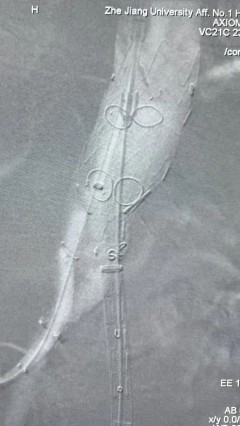

6. 解除束径,打开近端后释放,经肱动脉长鞘超选支架外分支,并进一步超选右侧肾动脉,交换加硬导丝,送入覆膜支架6*50mm和7*60mm各一枚,并予以球囊后扩张,手推造影显影良好。

7. 经长鞘重新选入左侧外分支,并超选进左肾动脉,沿导丝送入外周血管覆膜支架7*60mm一枚,并予以球囊后扩张,手推造影显影良好。

8. 从右侧股动脉入路送入腹主支架AB-24-12-110-S,近端重叠胸腹主动脉支架远端,调整好支架位置后释放。

9. 经左股动脉送入导丝导管,超选进腹主动脉支架短腿内,后沿导丝送入髂支,同理,右侧沿导丝送入髂支并释放,使用先健顺应性球囊后扩各支架连接处及支架近远端,最后通过预留导管向瘤腔注入人纤维蛋白粘合剂数支,造影显示分支通畅。